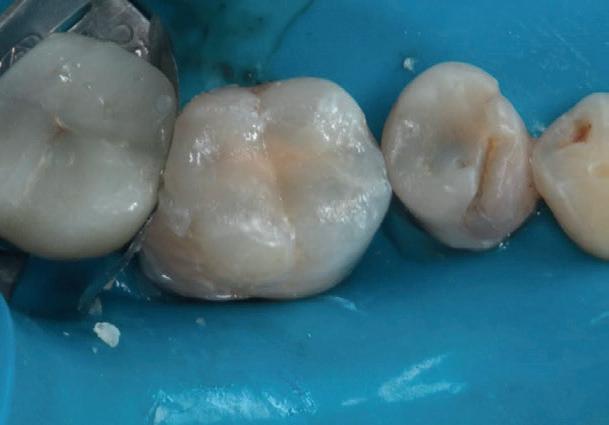

Un pacient caucazian în vârstă de 77 ani s-a prezentat la clinica autorului după cinci ani în care nu a fost la niciun control stomatologic. Examinarea clinică a arătat o pierdere semnificativă de os, parodontită cronică și multiple edentații care au destabilizat ocluzia. Pacientul a raportat sensibilitate la rece la nivelul primului molar drept inferior nr. 46, în special la ingerarea de lichide reci. Radiografia periapicală a confirmat constatările examenului clinic; în

plus, s-a detectat și prezența unei carii radiculare la nivelul rădăcinii distale a aceluiași molar, cu răspuns pozitiv la testul de sensibilitate (fig. 1-2).

Planul de tratament a început cu accent pe restabilirea sănătății parodontale. Într-o ședință ulterioară, odată cu îmbunătățirea stării parodonțiului, s-a efectuat restaurarea molarului nr. 46. Sub anestezie la Spina Spix pe partea dreaptă și

Figurile:

1. Situația clinică inițială.

2. Radiografia inițială.

3. Cavitate de clasa a II-a preparată.

4. Septomatrix pe poziție.

5. Cavitatea profundă.

izolarea cu digă de cauciuc, restaurarea din amalgam a fost îndepărtată complet și s-a obținut accesul la cavitatea carioasă (fig. 3-5). În ciuda proximității față de țesutul pulpar, nu a avut loc nicio expunere, iar cavitatea de clasa a II-a a fost restaurată complet cu Biodentine™ (fig. 6-8).